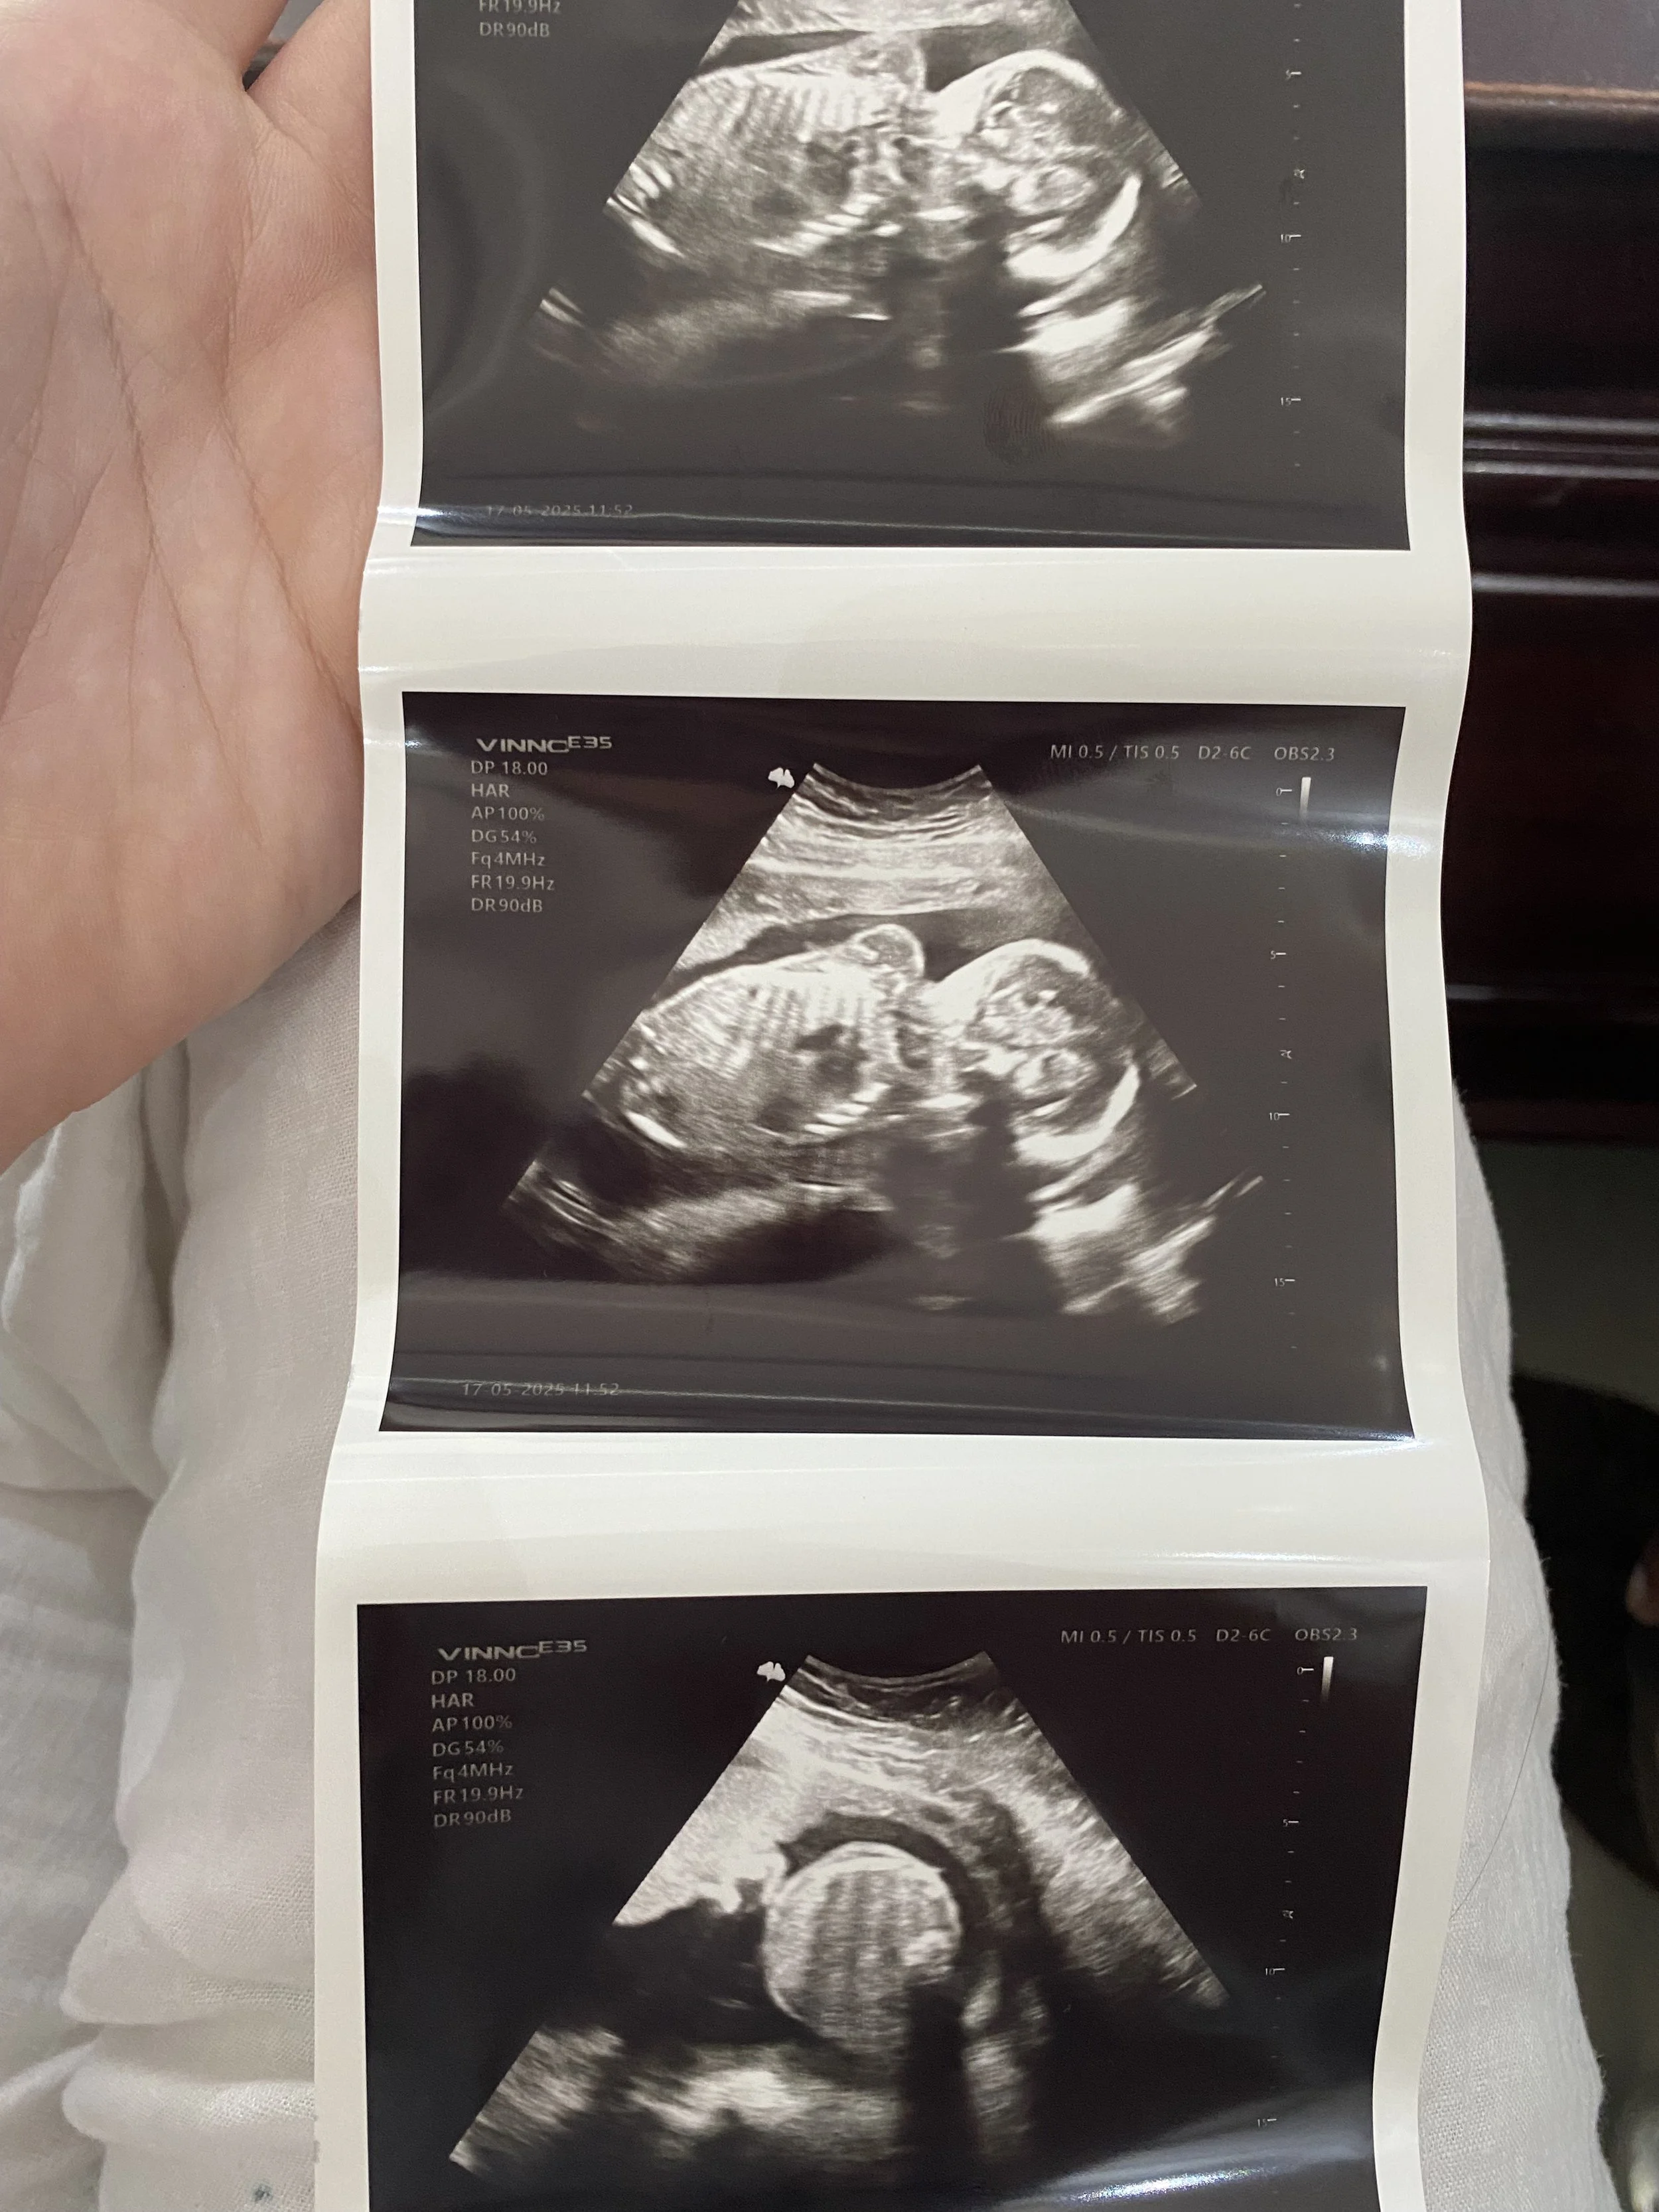

And Mthatha you may ask? Well, as is well known by now, we have been excited to announce that Baby Banda the 1st is on their way! We did say we had an “ever growing family”, lol. We found out on our very first night smack-dab in the middle of somewhere, a New Years Eve surprise, with fireworks in the neighboring village to celebrate. The Banda trio had begun.

The Lord has been so gracious through the process, and despite a scare or two in the early weeks, we landed upon an obstetrician in Mthatha where we have received good care. Our first appointment was at 7 weeks pregnant and Baby B measured just 1.07cm head to toe, already with a strong little heartbeat. This however marked the start of a very rough first 20 weeks of pregnancy with quite severe “morning” sickness (really, all day sickness) and debilitating fatigue. Women who charge through pregnancy with grace are a marvel to me, truly. I have never felt such a hollow version of myself, such a wreck - as if I were losing myself. I felt truly ill like I had contracted a deadly case of Scarlet Fever in the 50s. Despite the great hurdle those 5 months were the Lord brought us through and gave me much pleaded for release from most of my symptoms as we approached May… and most importantly, Baby B has developed beautifully and healthily - weighing 800g now, and has gone from 1cm to 36cm in length.